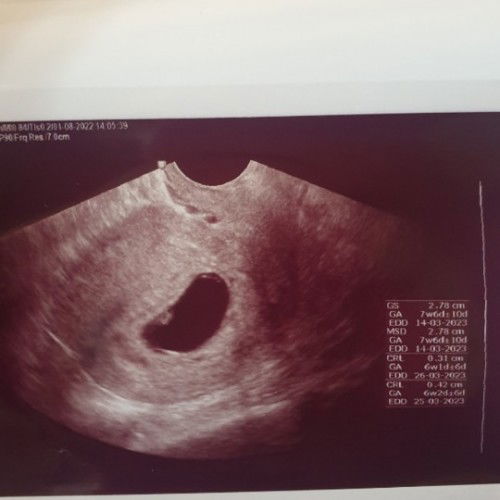

HPHT 22 MEI 2022. Gambar slide pertama, aku test pack H-3 sebelum haid Masih samar ,sampai slide ke 2 h-1 haid test pack pun masih samar. Akhirnya coba pakai clear blue emang the best deh langsung ketauan berapa week nya hihihi. Ternyata beneran positif. . Gambar slide 3, sabtu 25 juni 2022 akhirnya aku mutusin buat usg trans V di halomed.co.id (https://instagram.com/halomed.co.id?igshid=YmMyMTA2M2Y= ) lokasi kimia farma kebayoran lama (dokter nya enakk banget, cepet juga pelayanan nya ga sampe 10 menit nunggu udah dipanggil) harga nya pun masih kejankau 220rb. Dan kata dokter dari hasil usg ku yg masih sekitar 4week, memang masiu samar KANTUNG nya. Hihihi bunda bisa cek gmabar nya deh sambil zoom. Gapapa, yang penting aku udah mastiin ke dokter kalo kantungnya ada di rahim. Dan tidak ektopik (jujur takut banget ya bun, krna hamil pertama) . Terus dokter nanya, apakah aku ada keluhan? Alhamdulillah aku ga punya keluhan macem macem. Paling agak enek itu pun jarang banget muncul, dalam sehari pun blm tentu muncul, cuma laperan aja rasanya dan sering makan tiap bbrp jam dgn porsi dikit. Dan dokter cuma nyaranin aku minum vitamin buat kehamilan, aku info ke dokter aku udh minum prenatal dari natursplus gambar slide 4. Dan disini aku ga dikasih vitamin lain atau penguat kandungan. Mungkin krna aku ga ada keluhan apa apa dan usia skrg baru 24 tahun. . Dokter saranin aku buat balik lagi 4week kedepan, artinya di usia 8week deh kira kiraa. Katanya biar jelas kalo usia segitu. Oh iya, kemarin aku juga nanya prihal perlu gasih saya nambah susu hamil dok? Dokter bilang, vitamin yang aku konsumsi sudah sangat cukup buat nutrisi. Tapi rencana sih aku mau minum susu, krna aku tim suka kopi banget, jadi biar kealihin aja ganti kopi nya dengan susu hamil. Hehehe Sekian, semoga sharing ku membantu juga buat bunda yg hpl nya kurang lebih di bulan februari. #bantusharing #firstbaby